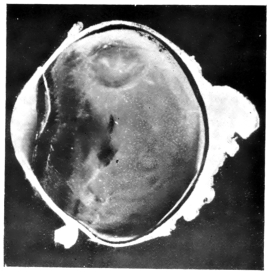

PLATE IV.

22.

LENS DISLOCATED BEHIND RETINA

curly bracket span

48

23.

FISTULA OF THE CORNEA

24.

CAPSULO-CORNEAL SYNECHIA

25.

RETINO-CORNEAL SYNECHIA

26.

SCLERAL FISTULA

27.

"    " (MAGNIFIED)